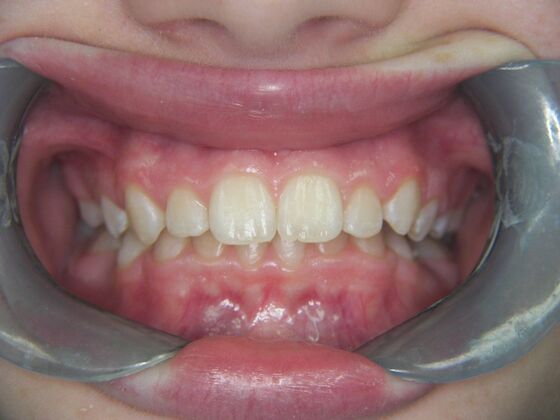

Patient is 9 years old and presents with 100% overbite and blocked out upper and lower lateral incisors. Both upper central incisors are palatally inclined causing a lack of space available for most anterior teeth. Advised her parents that she needs Phase I Interceptive Orthodontic treatment to provide room for all upper and lower front teeth. Phase I treatment was begun and finished, then began Phase II treatment shortly thereafter to finalize case. Removable retainer were fabricated for retention.